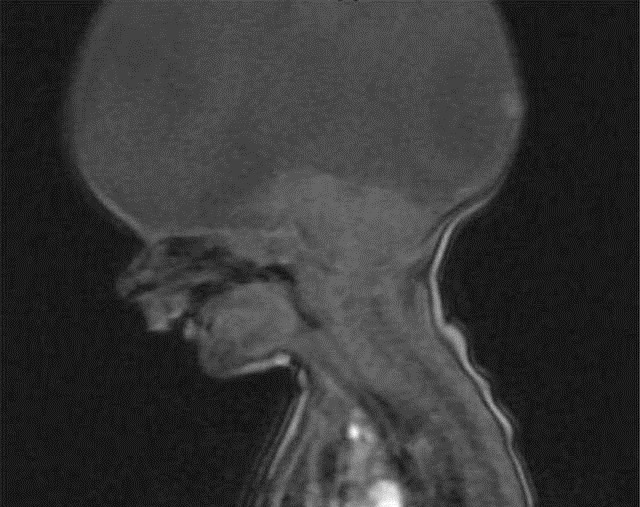

国外有一位母亲,为了让女儿有个伴,所以怀上了二胎,整个孕期产检都很正常,当天满怀希望期待孩子的降生时,医生却告诉她一个崩溃的消失:婴儿天生没有大脑。整个脑袋里装着的是脂肪类组织,而非大脑。医生建议孩子安乐死,因为婴儿很多功能都缺失,能活下去的概率很小。